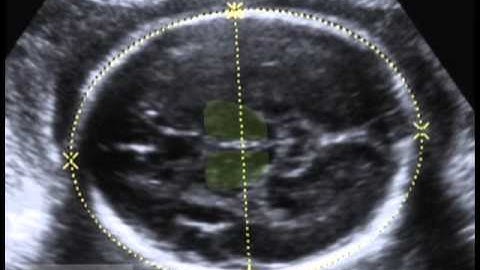

Sonographic recognition of normal fetal brain structures